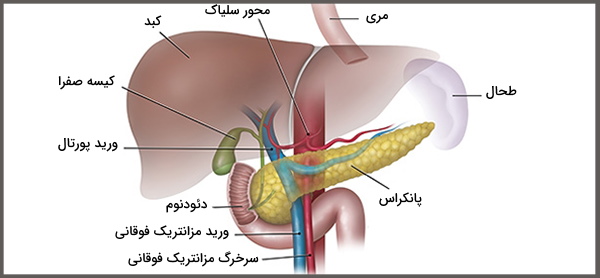

قیمت: 42٬000 تومان - دسته بندی فایل: پاورپوینتپاورپوینت اناتومی و فیزیولوژی پانکراس

فروش ویژه پاورپوینت حرفه ای اناتومی و فیزیولوژی پانکراس با تخفیف استثنایی فقط 55 هزار تومان تعداد اسلاید : 16 اسلاید